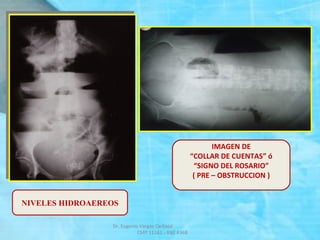

RADIOGRAFIA SIMPLE DE ABDOMEN

DE PIE Y DECUBITO

 Mejor valor diagnóstico.

 Se debe tomar en posición DE PIE

y DECUBITO, incluir diafragma

y pelvis.

 Rx. de PIE: NHA.

 Rx. de DECUBITO:

Gas Intraintestinal

ASAS YEYUNALES:

SIGNO

“PILA DE MONEDAS”

IMAGEN DE

“COLLAR DE CUENTAS” ó

“SIGNO DEL ROSARIO”

( PRE – OBSTRUCCION )

NIVELES HIDROAEREOS